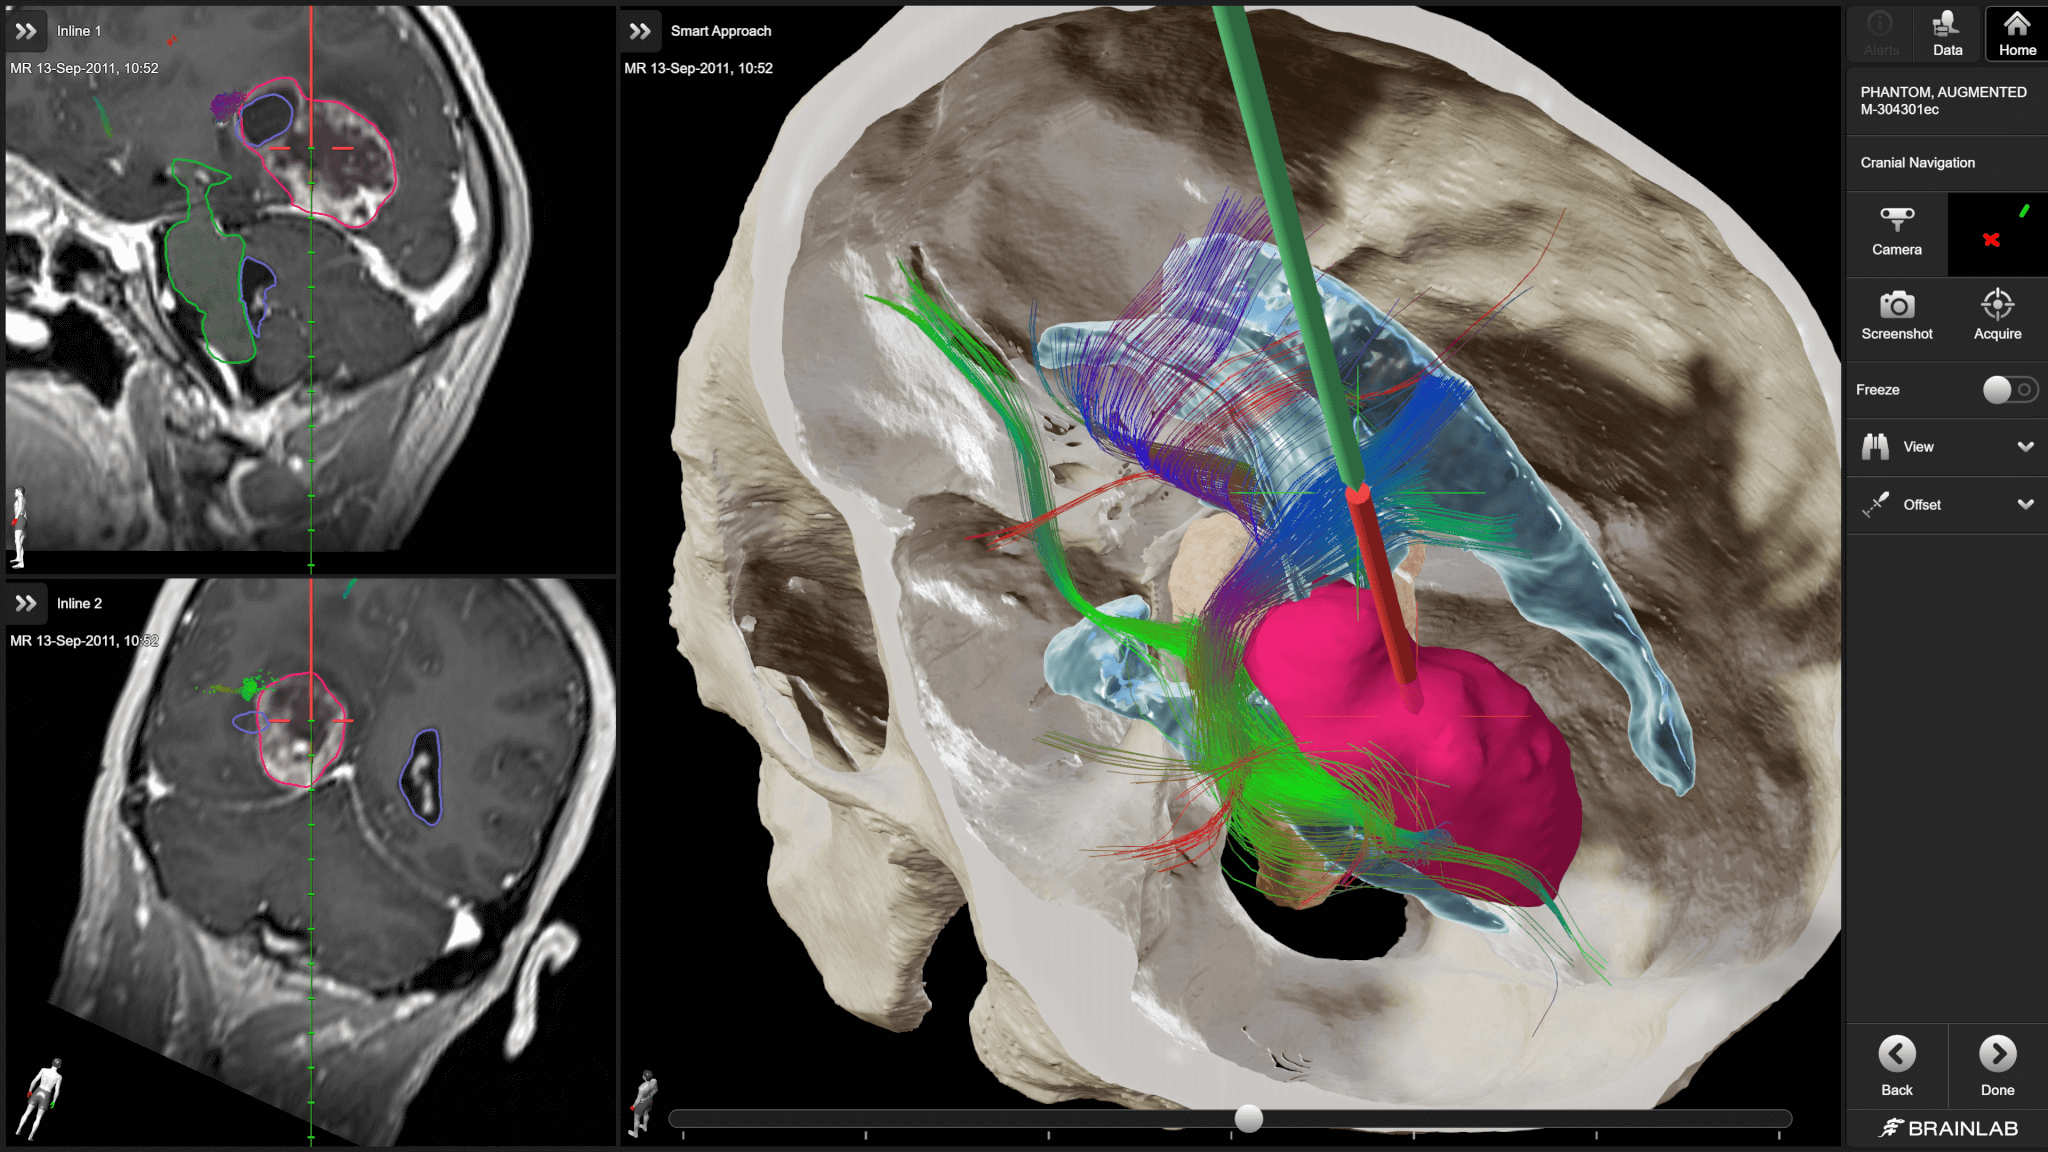

Brainlab neuronavigation combines ease of use with extended functionality tailored to surgeons’ needs